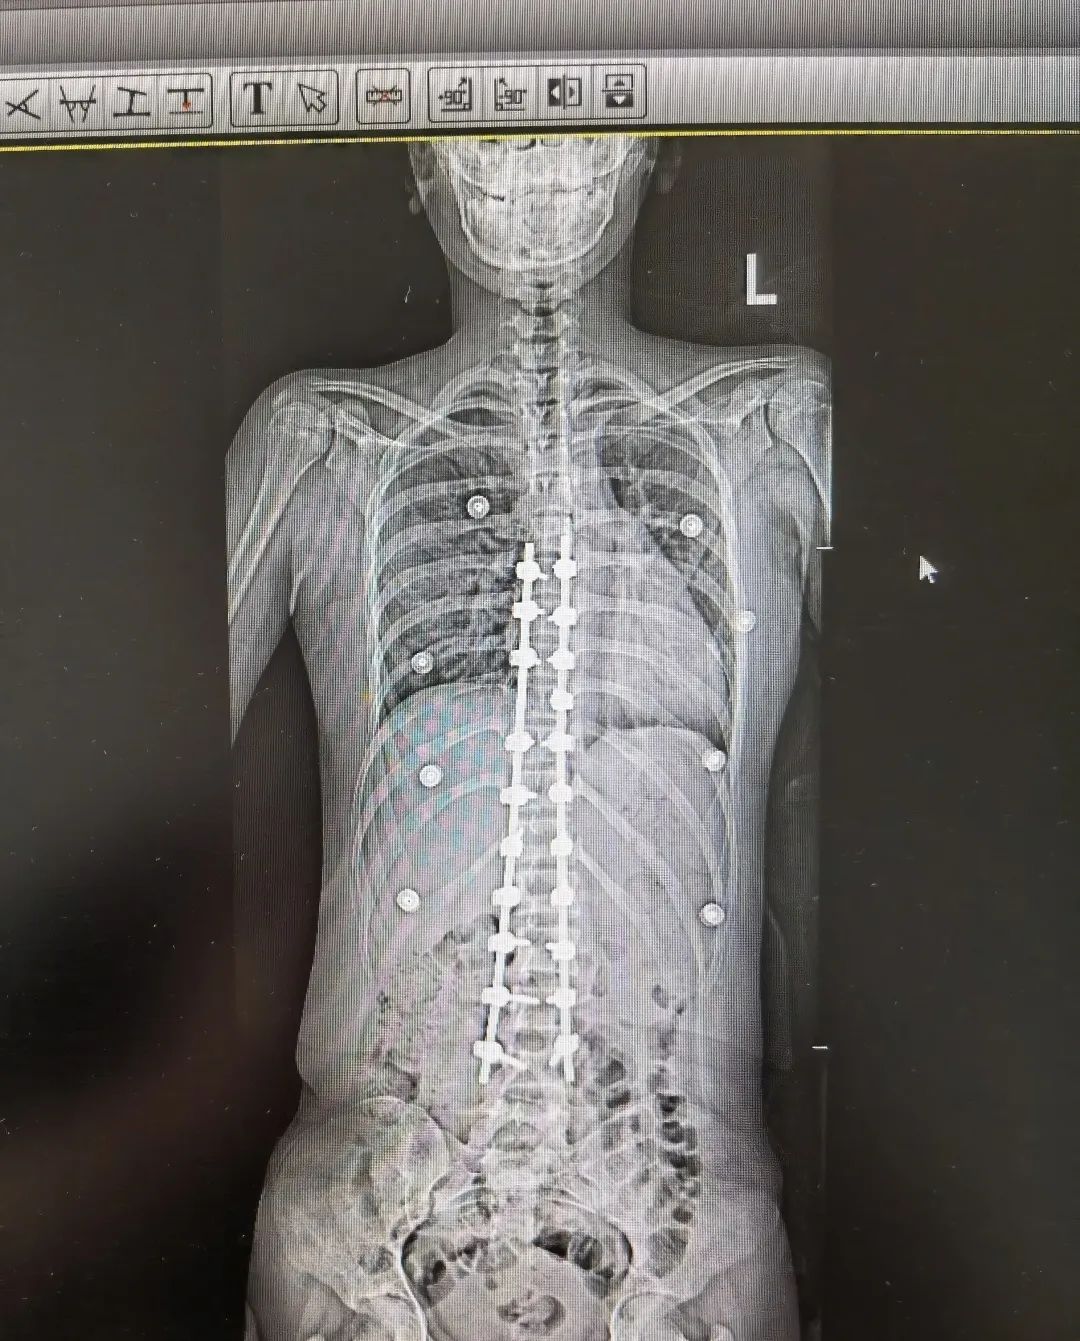

青少年特发性脊柱侧弯术前术后图

暑假,骨科病房里和梦梦一样的孩子还有7个,都是因为严重的青少年特发性脊柱侧弯陆续入院。

“在所有脊柱侧弯类型中,临床中占比最高、最常见的就是青少年特发性脊柱侧弯,约占脊柱侧弯的百分之70%。目前它的发病原因尚不清楚,可能与遗传、免疫、激素、姿势不良等因素有关,往往从10岁左右开始发病。根据严重程度不同,治疗方案也有差异。部分患儿可以采用支具矫形、物理康复锻炼等方式进行保守治疗,但是如果侧弯度数大于40°,就需要考虑手术矫形。”

陈文昊副主任表示,虽然青少年特发性脊柱侧弯目前病因不明,但部分患有青少年特发性脊柱侧弯的孩子都有一个特点——短时间内长得都比较快。青春期骨骼快速生长发育,原本轻微的脊柱侧弯此时也会迅速进展,一年甚至可长歪10度以上。